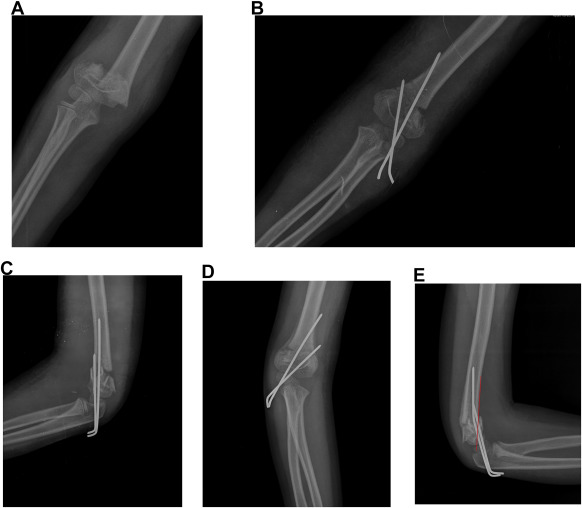

Pin-spread distance (PSD) and pin-spread ratio (PSR) at the fracture were measured using postoperative AP radiography. PSD is the measurement of the distance in the coronal plane between the pins at the fracture site (Fig. 2 ). When more than 2 pins were present, this distance was measured between the most distant pins. PSR was obtained by dividing PSD by the coronal length of the humerus at the fracture.18

Fig. 2

Fig. 2.

Pin-spread measurement at the level of the fracture. AB represents the coronal width of the humerus at the fracture site, while CD represents pin-spread distance.